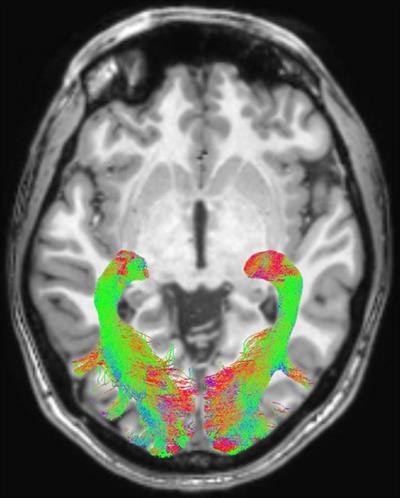

The group found statistically significant abnormalities within the visual system brain structures of patients with Parkinson's disease, compared with the healthy control subjects. These included changes in optic radiations, reduced white-matter concentration, and reduced optic chiasm volume.

Left and right optic radiation image is overlaid onto a T1-weighted axial volume image. Optic radiation images were obtained based on diffusion-weighted volume images through constrained spherical deconvolution fitting and related tractography. Each bundle was automatically colored according to tract main directionality: red for left to right, green for anterior to posterior, and blue for inferior to superior. Image courtesy of the RSNA."This protocol could be used for longitudinal studies to help understand the progression of visual alterations in the course of the disease and to assess positive or negative effects of pharmacologic treatments on visual structures," the authors wrote.